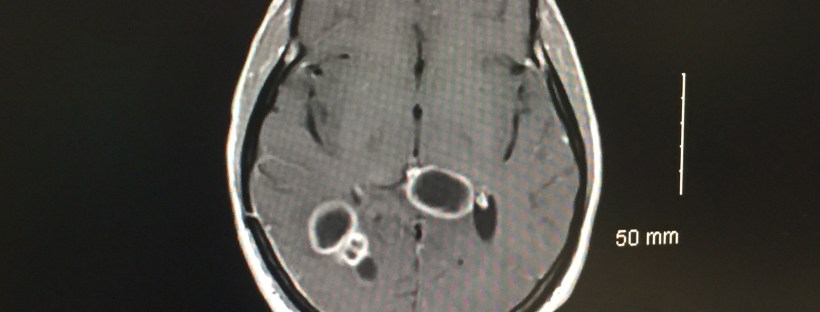

Yesterday was Clay’s second infusion of Avastin. Because the first MRI after radiation and chemo showed that the tumor had grown slightly, even during treatment, the doctors all agreed that adding an additional drug was the right decision.

We go next Wednesday for another MRI. Dr. Weinberg asked us to have one only a month after the first. We will go in the morning for the test and get the results just after lunch. We are praying that it gone. But, if it’s not gone, we are praying that there is no new growth. Of course, I will update you when we know something.